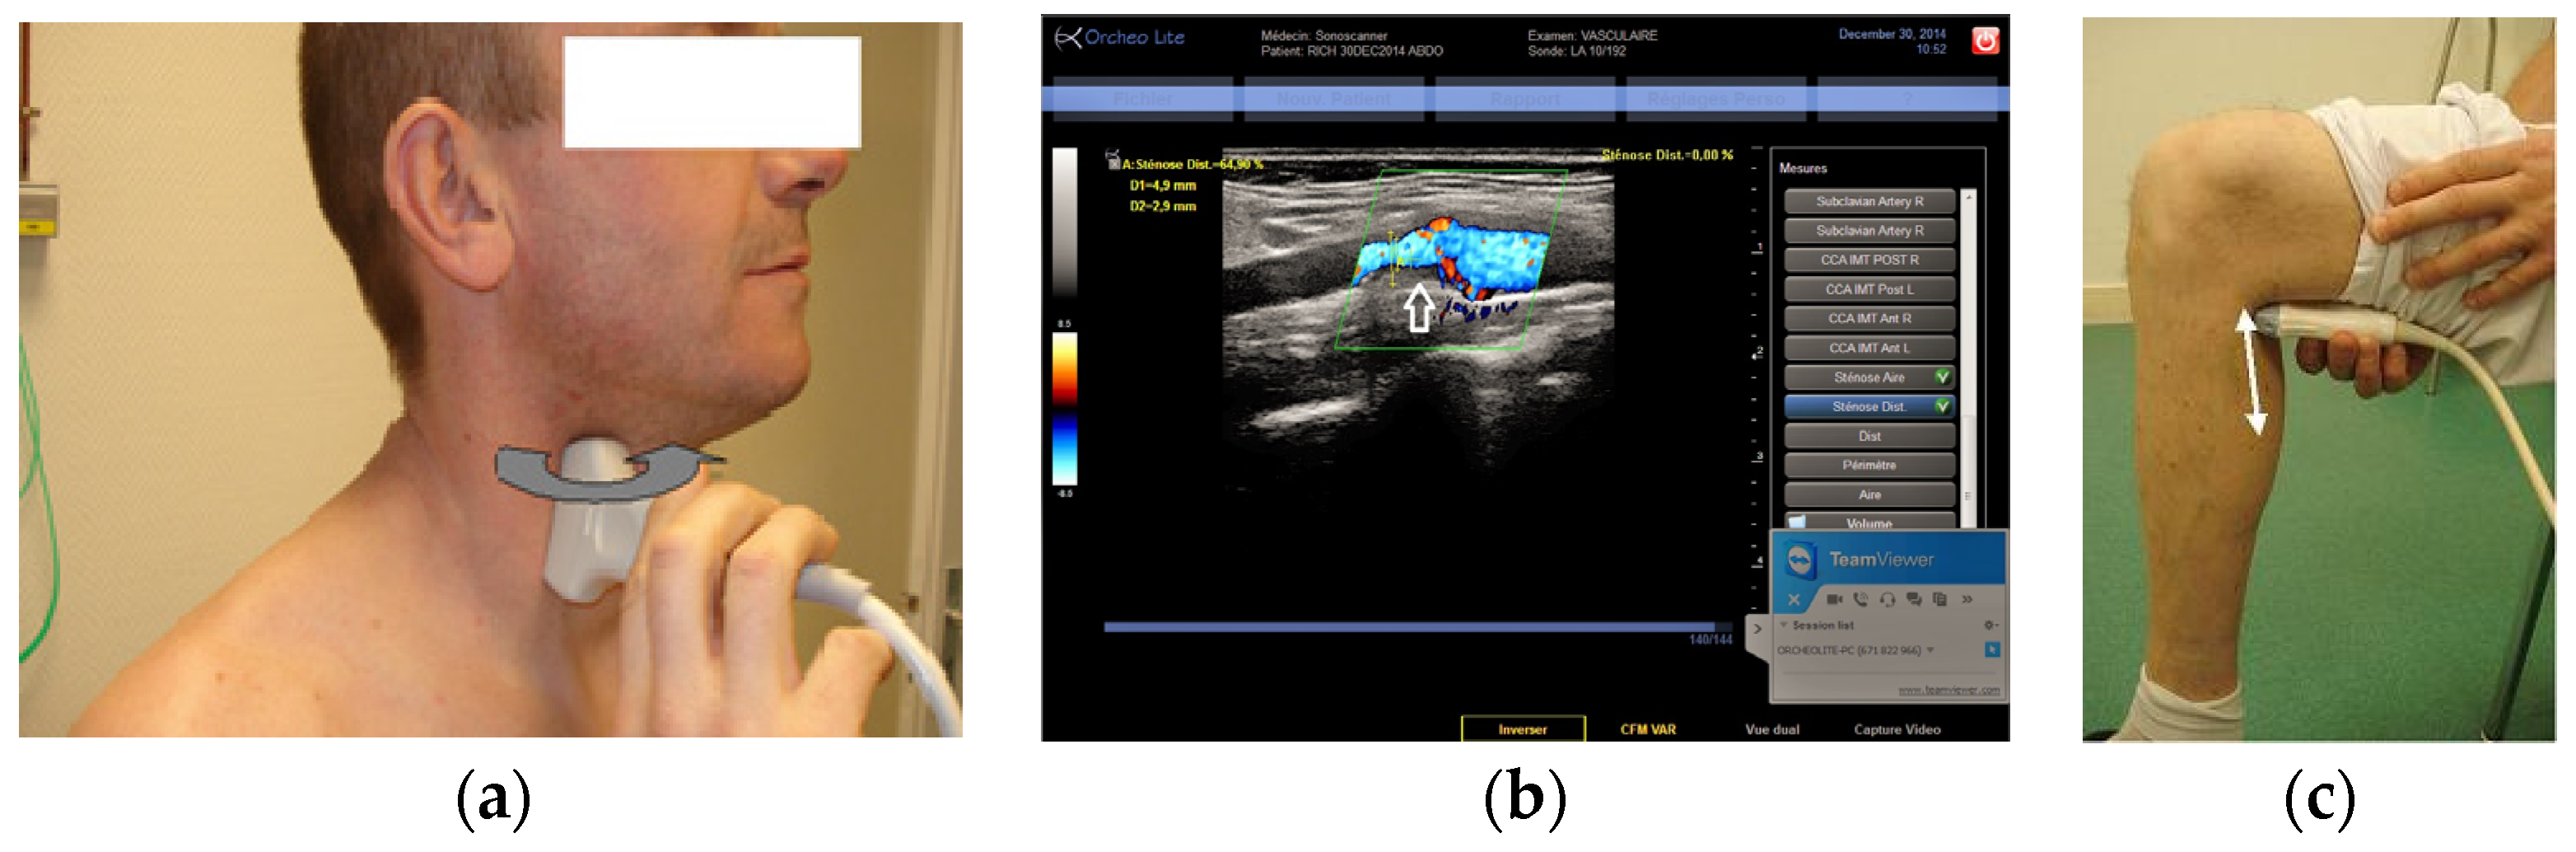

Figure 5. (a) Remote guidance (RG) for carotid artery; (b) View of a carotid stenosis in color Doppler by RG; (c) Location of the probe for calf vein visualization with RG.

4.3. Superficial Vessel Examinations

In both phases of the study, RG was found to be the most appropriate for assessments of superficial blood vessels. In contrast to the other methods of tele-echography assessed, RG did require training of the non-sonographer operator. However, it was noted over the course of this investigation that, with one week of training, the non-sonographer operator could become sufficiently proficient at obtaining long and short axis views of superficial vessels. It is very easy for any operator, even a non-sonographer, to visualize a cross-sectional view (black circle in the image) of a superficial artery or vein. With training, the operator was then able to rotate the probe 90 degrees to turn the transverse image of a dark beating circle into the long rectangular black area of a longitudinal image. Under the direction of the expert sonographer, the non-sonographer operator then translated the probe to the appropriate position (e.g., carotid bifurcation) and adjusted the probe to obtain a clear longitudinal image for diagnosis.

During the first phase of the study, the 7 MHz probe was available for use with the RA and RG. In this case, RG was chosen as the most appropriate method due to the size and weight limitations of the RA and the ability of RG to provide images for diagnoses. In the second phase, a higher frequency 17 MHz two-dimensional (2D) probe was available for RG examinations where only a 10 MHz probe was available for the MP system. In this case, RG was again chosen as the most appropriate method for superficial vessel examinations as the higher frequency of the transducer provided images of better quality for diagnoses. Additionally, the higher frequency probe (like every conventional probe) used with RG has a narrow head which allows the operator to reduce the distance between the vessels of interest and the probe transducer by applying slight pressure, thereby improving image quality. In contrast, the head of the motorized probe is much wider and does not allow for a similar maneuver. Thus, it was agreed that for superficial vessels (carotid artery, leg artery and veins), priority should be placed on the echographic performance of the probe (high frequency, narrow foot print) rather than teleoperation ability.

During the second phase of the study, the ability of the expert sonographer to teleoperate the echograph at the patient site proved to be a real advantage. With RG the non-sonographer operator is generally required to control all the echograph functions and settings under the verbal direction of the expert sonographer. This requires additional training and skill of the operator to maintain the proper image (fix the hand orientation) while making adjustments on the echograph. The introduction of the teleoperated echograph in the second phase of the study allowed the non-sonographer operator to focus on maintaining the proper image (hand motionless) while the expert controlled the echograph functions and settings (for example. Doppler, gain, video and image saving, measurements). This resulted in more efficient examinations with shorter examination times.